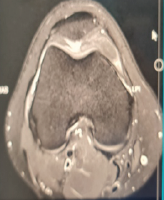

Over time, she experienced worsening pain and functional limitations, particularly during daily tasks such as food preparation, toileting, and personal hygiene, which significantly reduced her quality of life. Clinical evaluation demonstrated FE of 130°, abduction of 130°, external rotation (ER) of 40°, and IR to the L3 vertebral level. Strength testing showed values of 20.1 N for FE, 24.3 N for abduction, 22.7 N for ER, and 27.9 N for IR. Patient-reported outcomes indicated moderate disability, with a visual analogue scale (VAS) score of 6/10, a constant score of 56/100, and the American Shoulder and Elbow Surgeons (ASES) score of 59/100. Radiographs revealed advanced glenohumeral osteoarthritis with joint space narrowing and superior migration of the humeral head. Magnetic resonance imaging demonstrated humeral head cartilage loss, glenoid wear, and an intact, well-preserved latissimus dorsi transfer (Fig. 2). Considering the severity of osteoarthritis and persistent symptoms, rTSA was performed with preservation of the prior LDT.

Figure 2: Radiographs and magnetic resonance imaging 10 years after anterior latissimus dorsi tendon transfer. (a) Anteroposterior and (b) axil radiograph of left shoulder demonstrating advanced glenohumeral osteoarthritis with joint space narrowing and superior migration of the humeral head. (c) Coronal and (d) axial T2-weighted magnetic resonance image showing well-preserved transferred latissimus dorsi tendon attached to the lesser tuberosity.